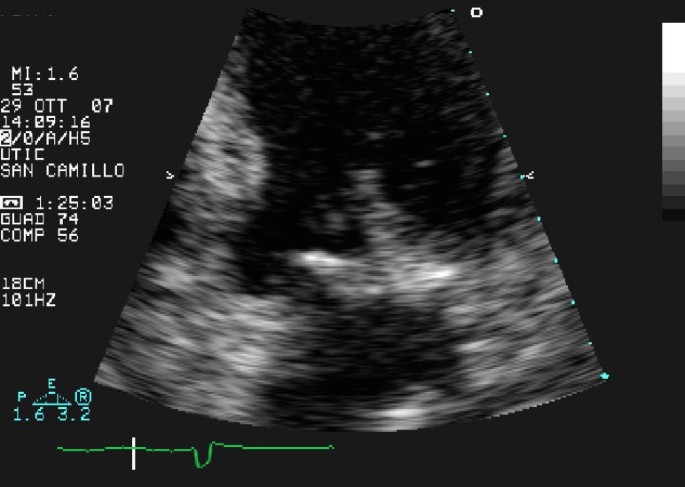

Transthoracic echocardiography (TTE) revealed a calcified mitral annulus with an echo-dense spherical, tumor-like mass, located close to the posterior leaflet (Figure 1). A typical vegetation was located at the base of the posterior mitral leaflet, especially on the ventricular surface (Figure 2). These findings confirmed the diagnosis of IE associated with MAC. On Doppler color-flow mapping, a mild mitral regurgitation was seen in the left atrium; no obstruction to the diastolic transmitral flow was found. The left ventricle was dilated with akinesia of the apex and hypokinesia of the other segments and an ejection fraction of 30%. The right ventricle and right atrium were normal. The aortic valve was tricuspid and showed some calcification.